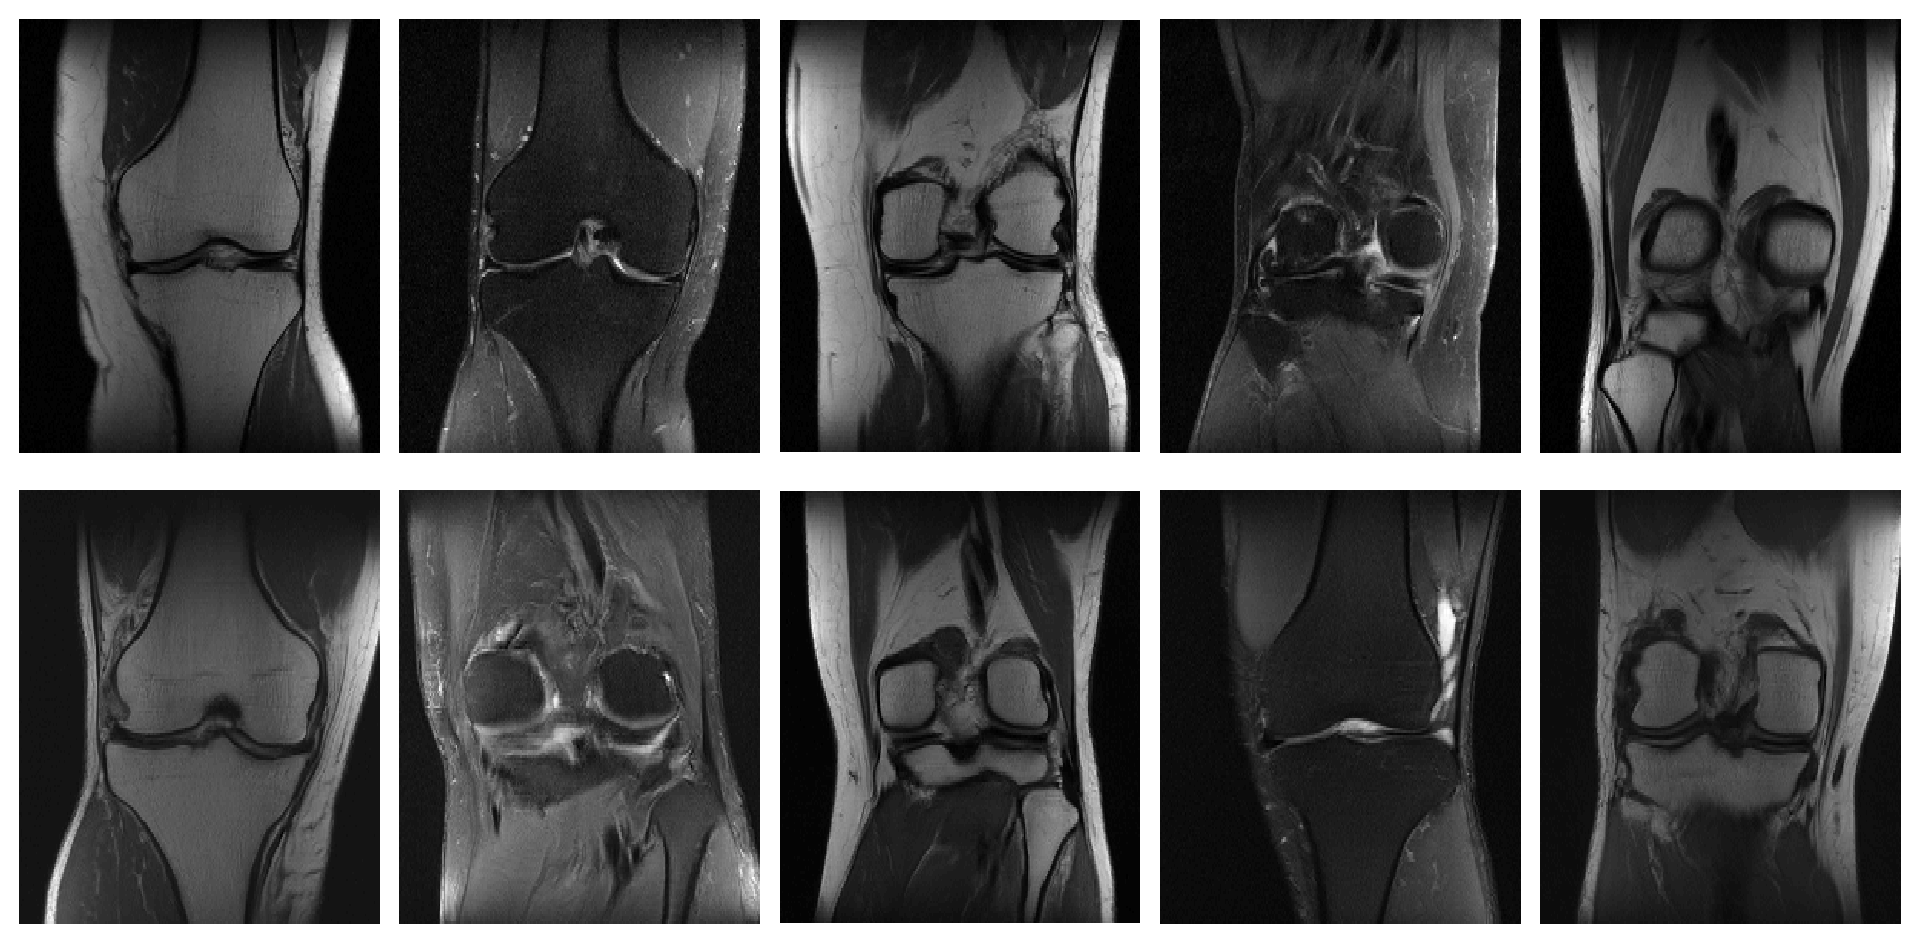

After the ProGAN was trained, the images produced by the generator highly resembled the true knee images in the training dataset. For visual comparison, samples of images from the training dataset as well as samples of images generated by the ProGAN after training, cropped to the central region of interest (ROI), are shown in Fig. 3.

Refer to caption

Figure 3: (Top) Samples from knee MRI images in the training dataset (Bottom) Samples from generated knee MRI images after training with the ProGAN